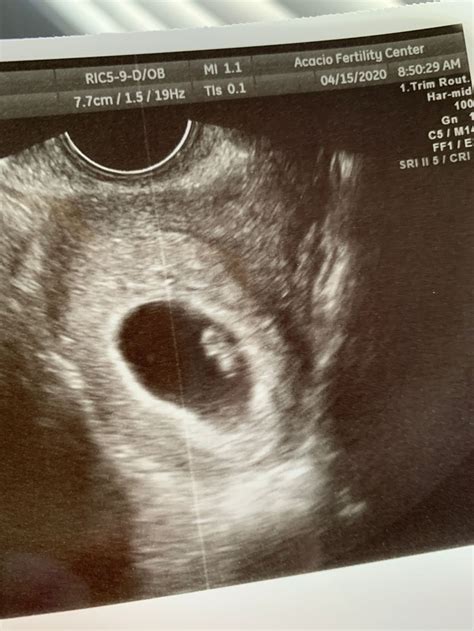

The 6 weeks ultrasound is typically performed transvaginally, as the embryo is still very small and an abdominal ultrasound may not provide clear images. This procedure involves inserting a probe into the vagina to get a closer view of the uterus and the developing embryo. The ultrasound technician will look for several key indicators of a healthy pregnancy at this stage.

• Gestational Sac: This is the first structure that can be seen on an ultrasound. It appears as a small, fluid-filled sac within the uterus.

• Yolk Sac: This structure is crucial for the early development of the embryo. It provides essential nutrients and helps in the formation of the early circulatory system.

• Embryo: At 6 weeks, the embryo itself is very small, often measuring around 2-4 millimeters in length. It will appear as a tiny, curved structure within the gestational sac.

• Fetal Pole: This is the earliest visible sign of the developing embryo. It appears as a thickened area within the yolk sac.

• Heartbeat: In some cases, a fetal heartbeat may be detected at this stage, although it is more commonly seen at 7 weeks. The heartbeat is a reassuring sign of a healthy pregnancy.

• Size and Shape: The gestational sac should be round and well-defined. The yolk sac should be visible within the sac, and the embryo should be clearly distinguishable.